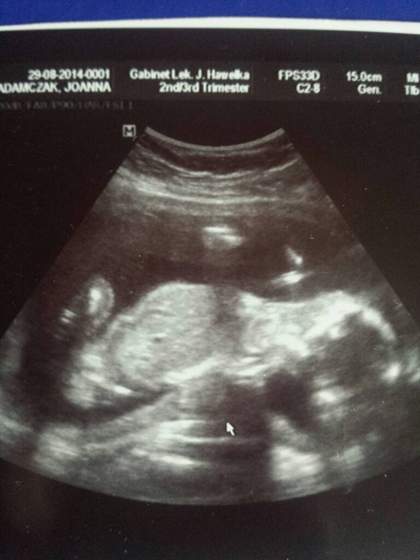

DOROTAV z ostatniej wizyty mam zdjęcie tylko glowki i kości udowej bo Zosia sie tak wierci że gin nie może uchwycić jej całej :-P Więc wstawiam focie z 29 sierpnia tj. 20 tc

Załączniki

• 1411457728000.jpg

1411457728000.jpg

20,9 KB · Wyświetleń: 74